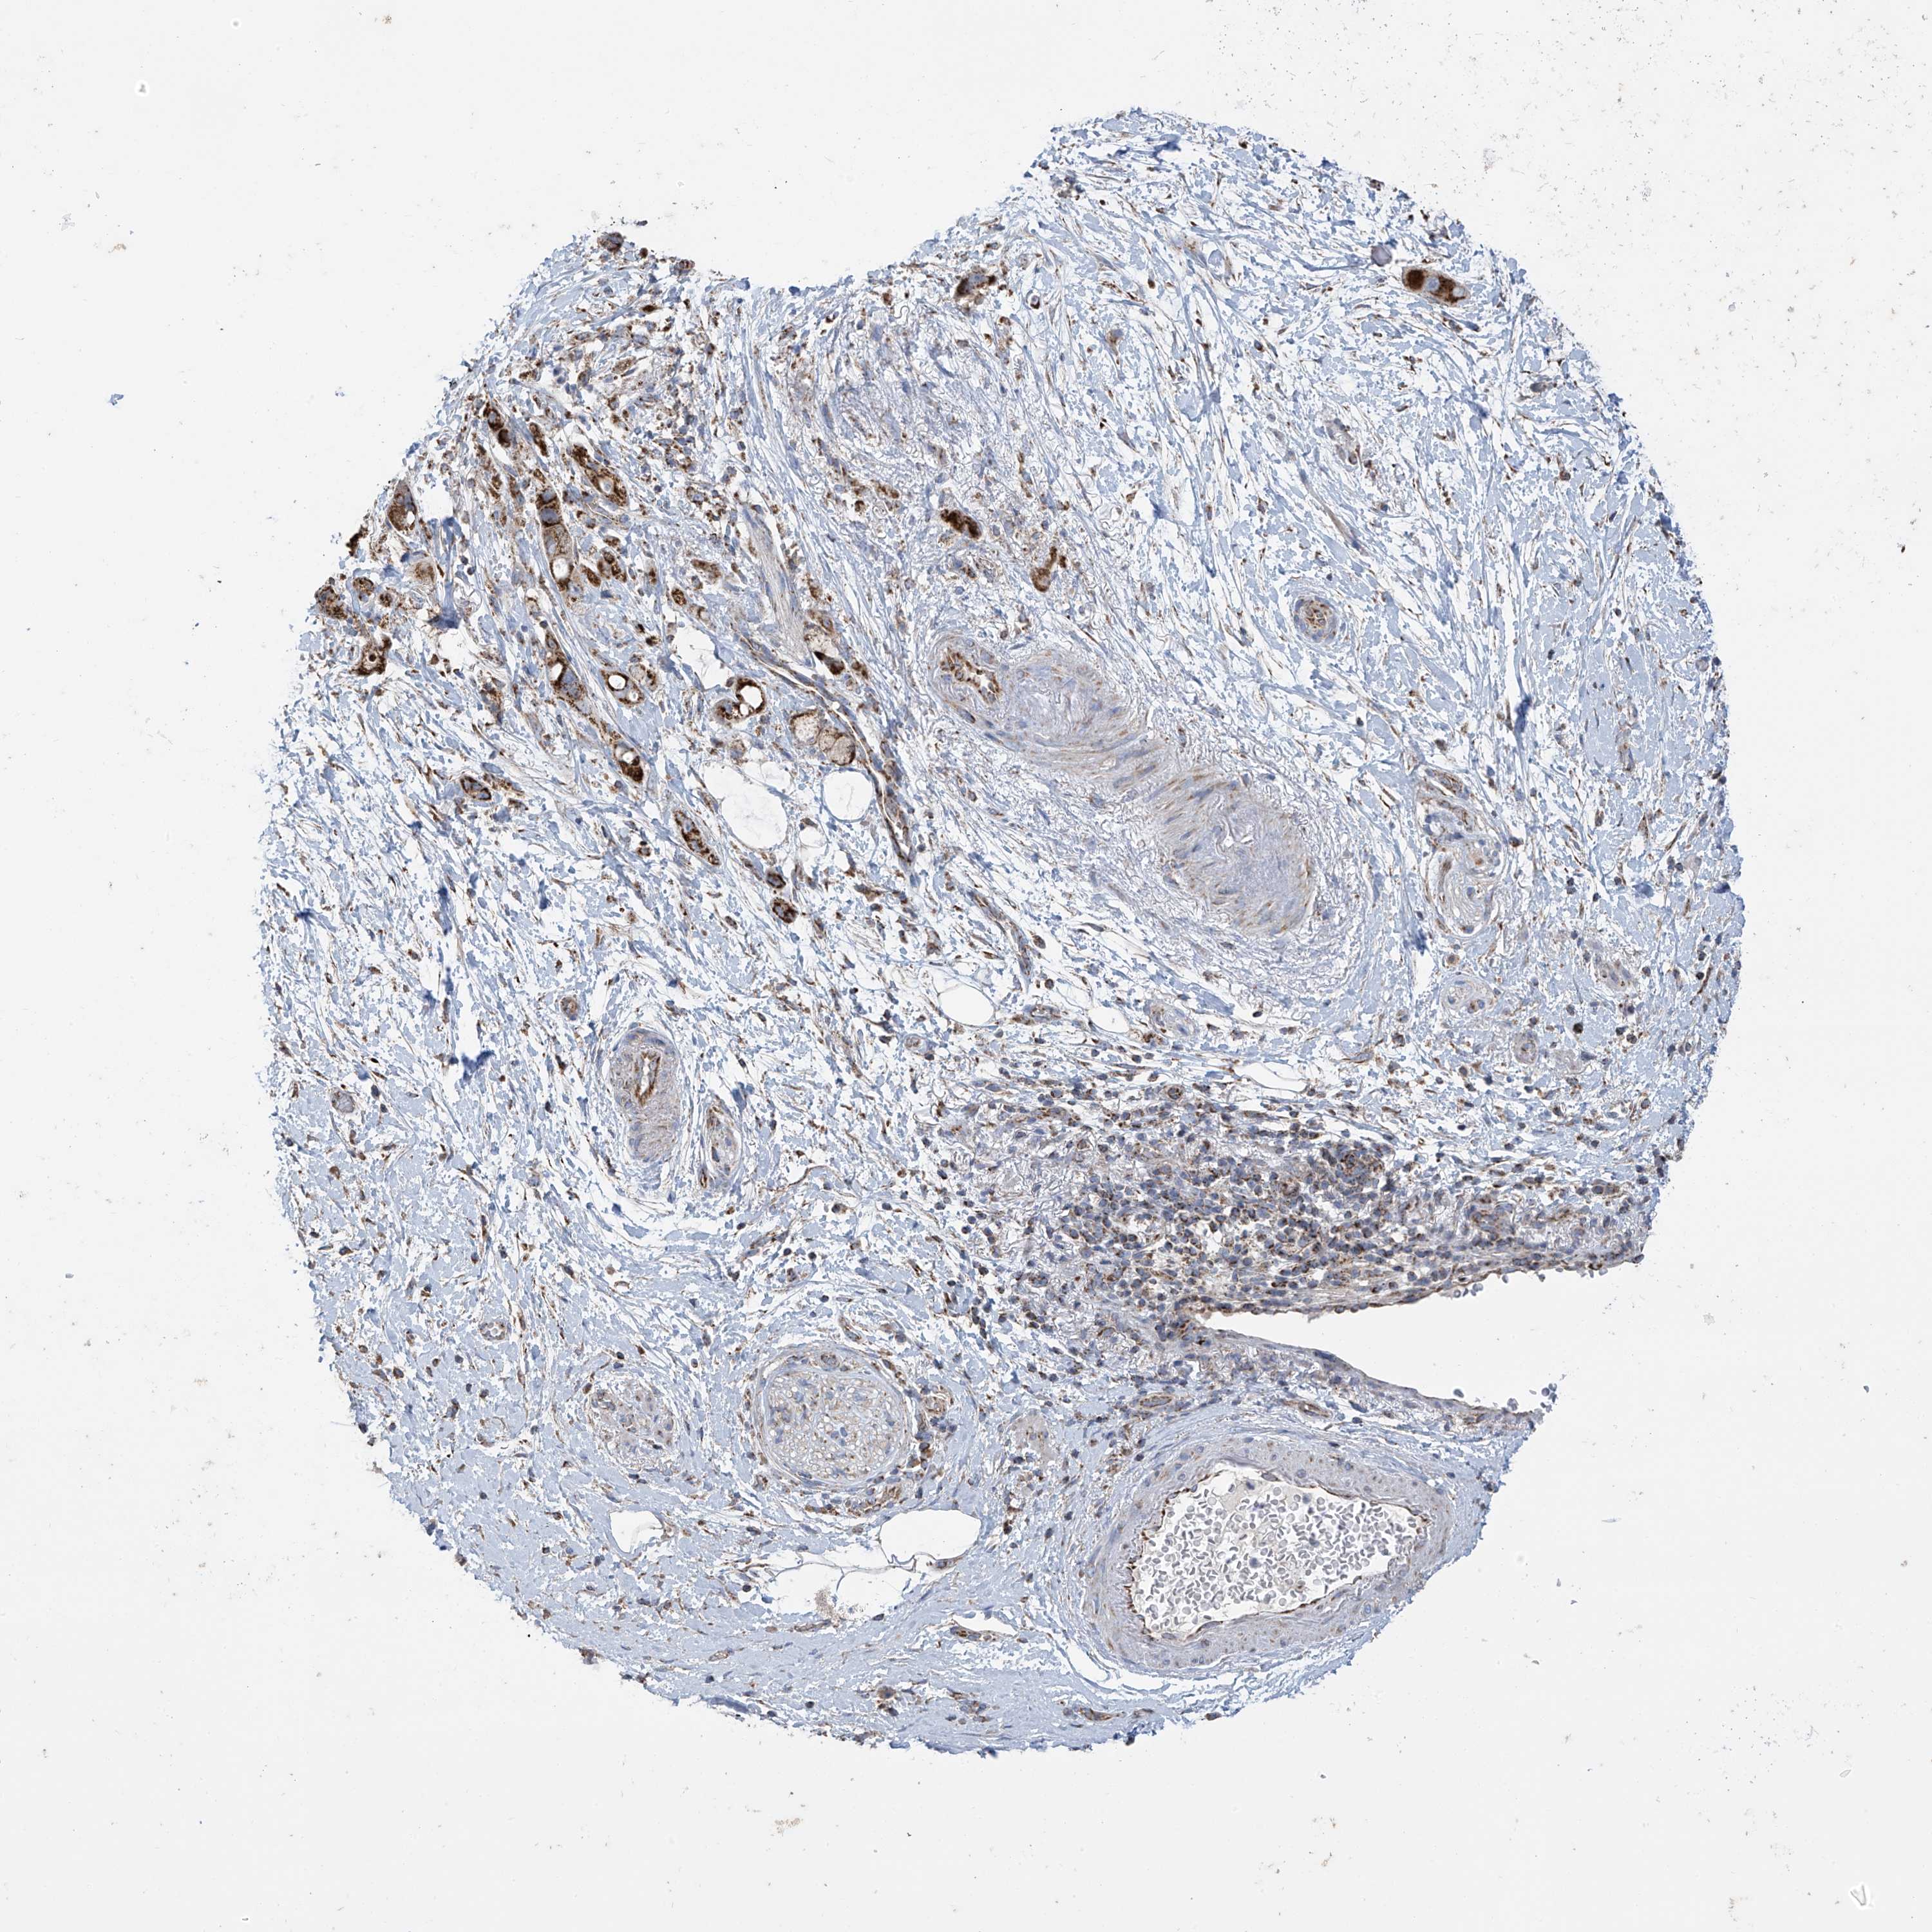

PANCREATIC CANCER - Protein expressioni

A mouse-over function shows sample information and annotation data. Click on an image to view it in a full screen mode. Samples can be filtered based on level of antibody staining by selecting one or several of the following categories: high, medium, low and not detected. The assay and annotation is described here.

Note that samples used for immunohistochemistry by the Human Protein Atlas do not correspond to samples in the TCGA dataset.

Antibody stainingi

Antibody staining in the annotated cell types in the current human tissue is reported as not detected, low, medium, or high, based on conventional immunohistochemistry profiling in selected tissues. This score is based on the combination of the staining intensity and fraction of stained cells.

Each image is clickable and will lead to virtual microscopy that enables deeper exploration of all samples and also displays staining intensity scores, fraction scores and subcellular localization as well as patient and tissue information for each sample.

Antibody HPA034602

Antibody HPA034603

Antibody CAB033424

Staining

High

Medium

Low

Not detected

Intensity

Strong

Moderate

Weak

Negative

Quantity

>75%

75%-25%

<25%

None

Location

Nuclear

Cytoplasmic/membranous

Cytoplasmic/membranous,nuclear

Adenocarcinoma, NOS